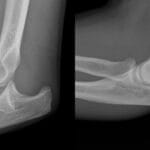

A 4-year-old girl complains of pain and swelling in her left upper calf area. An anteroposterior (AP) radiograph reveals a lobular lytic lesion in the proximal tibial meta-diaphysis (indicated by arrows) with a solid periosteal response (indicated by an arrowhead). Sagittal T2-weighted fast spin-echo (FSE) and axial SPAIR MR images (c) depict a solid lesion in the proximal tibia (indicated by arrows) accompanied by soft tissue oedema (indicated by arrowheads). Initially misdiagnosed as TOS by Reader 1, the lesion was later histologically confirmed as an ABC.